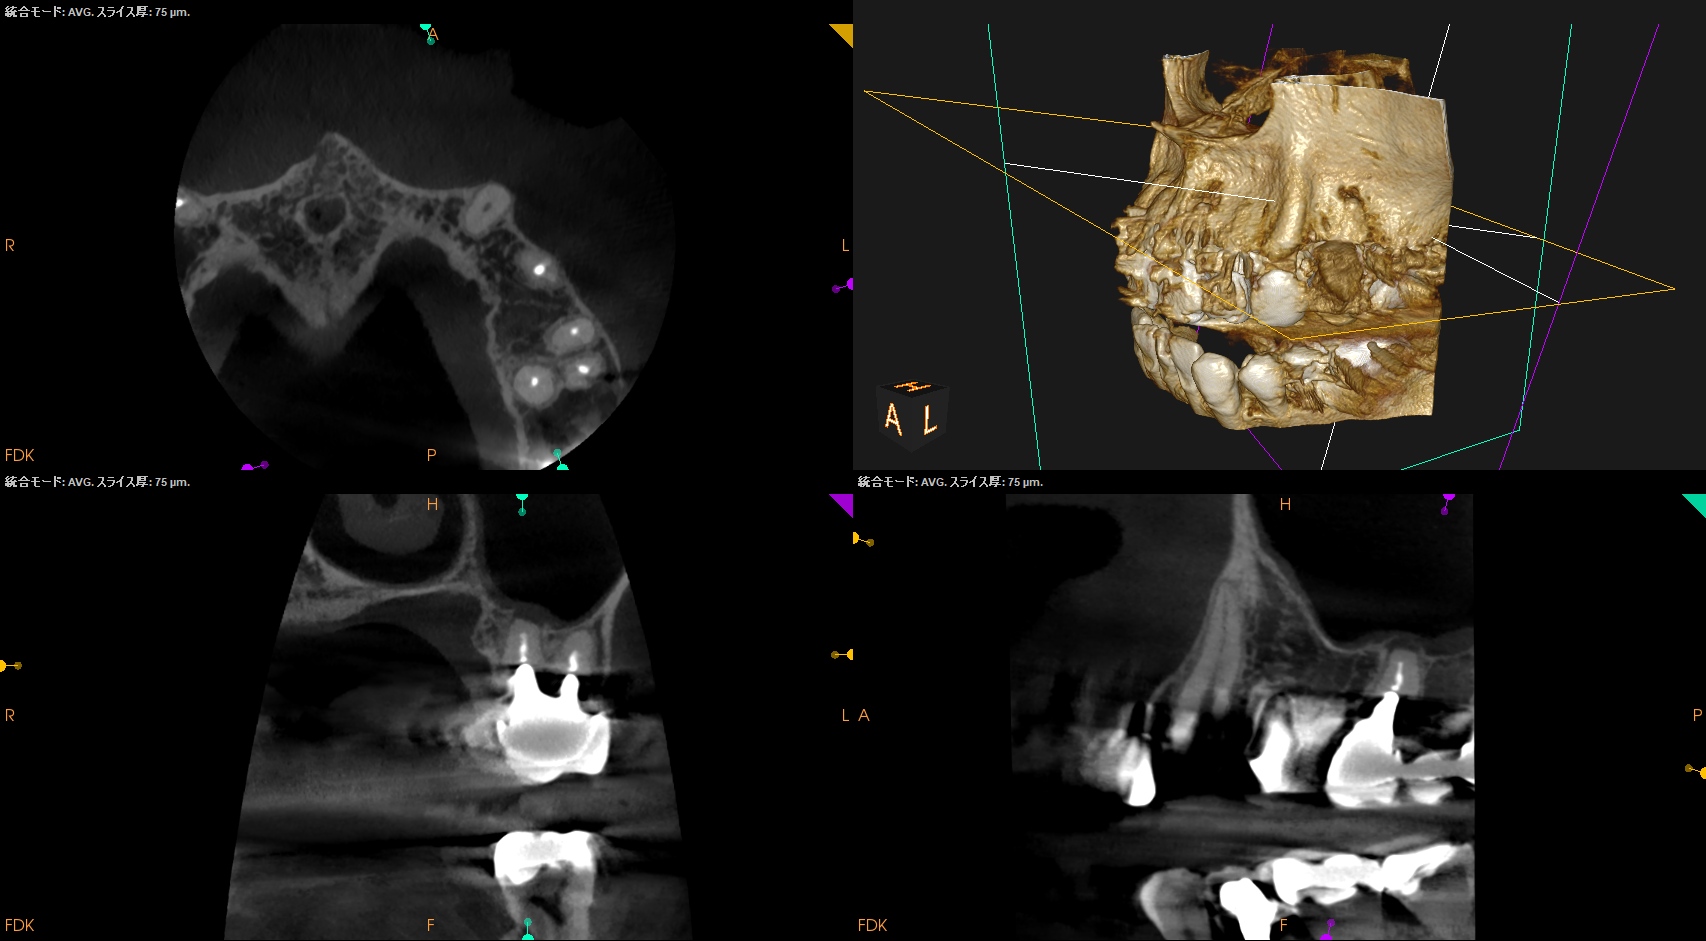

CBCT(2024.7.1)

#3

MB

DB

P

MB,DB,Pと3根全てに病変がある。

しかも形成が不完全だ。

再根管治療が濃厚である。

#14

MB,DBには病変がないが、Pに存在する。

これは頭が痛い。

パラタルフラップも困難なケースだからだ。

#16